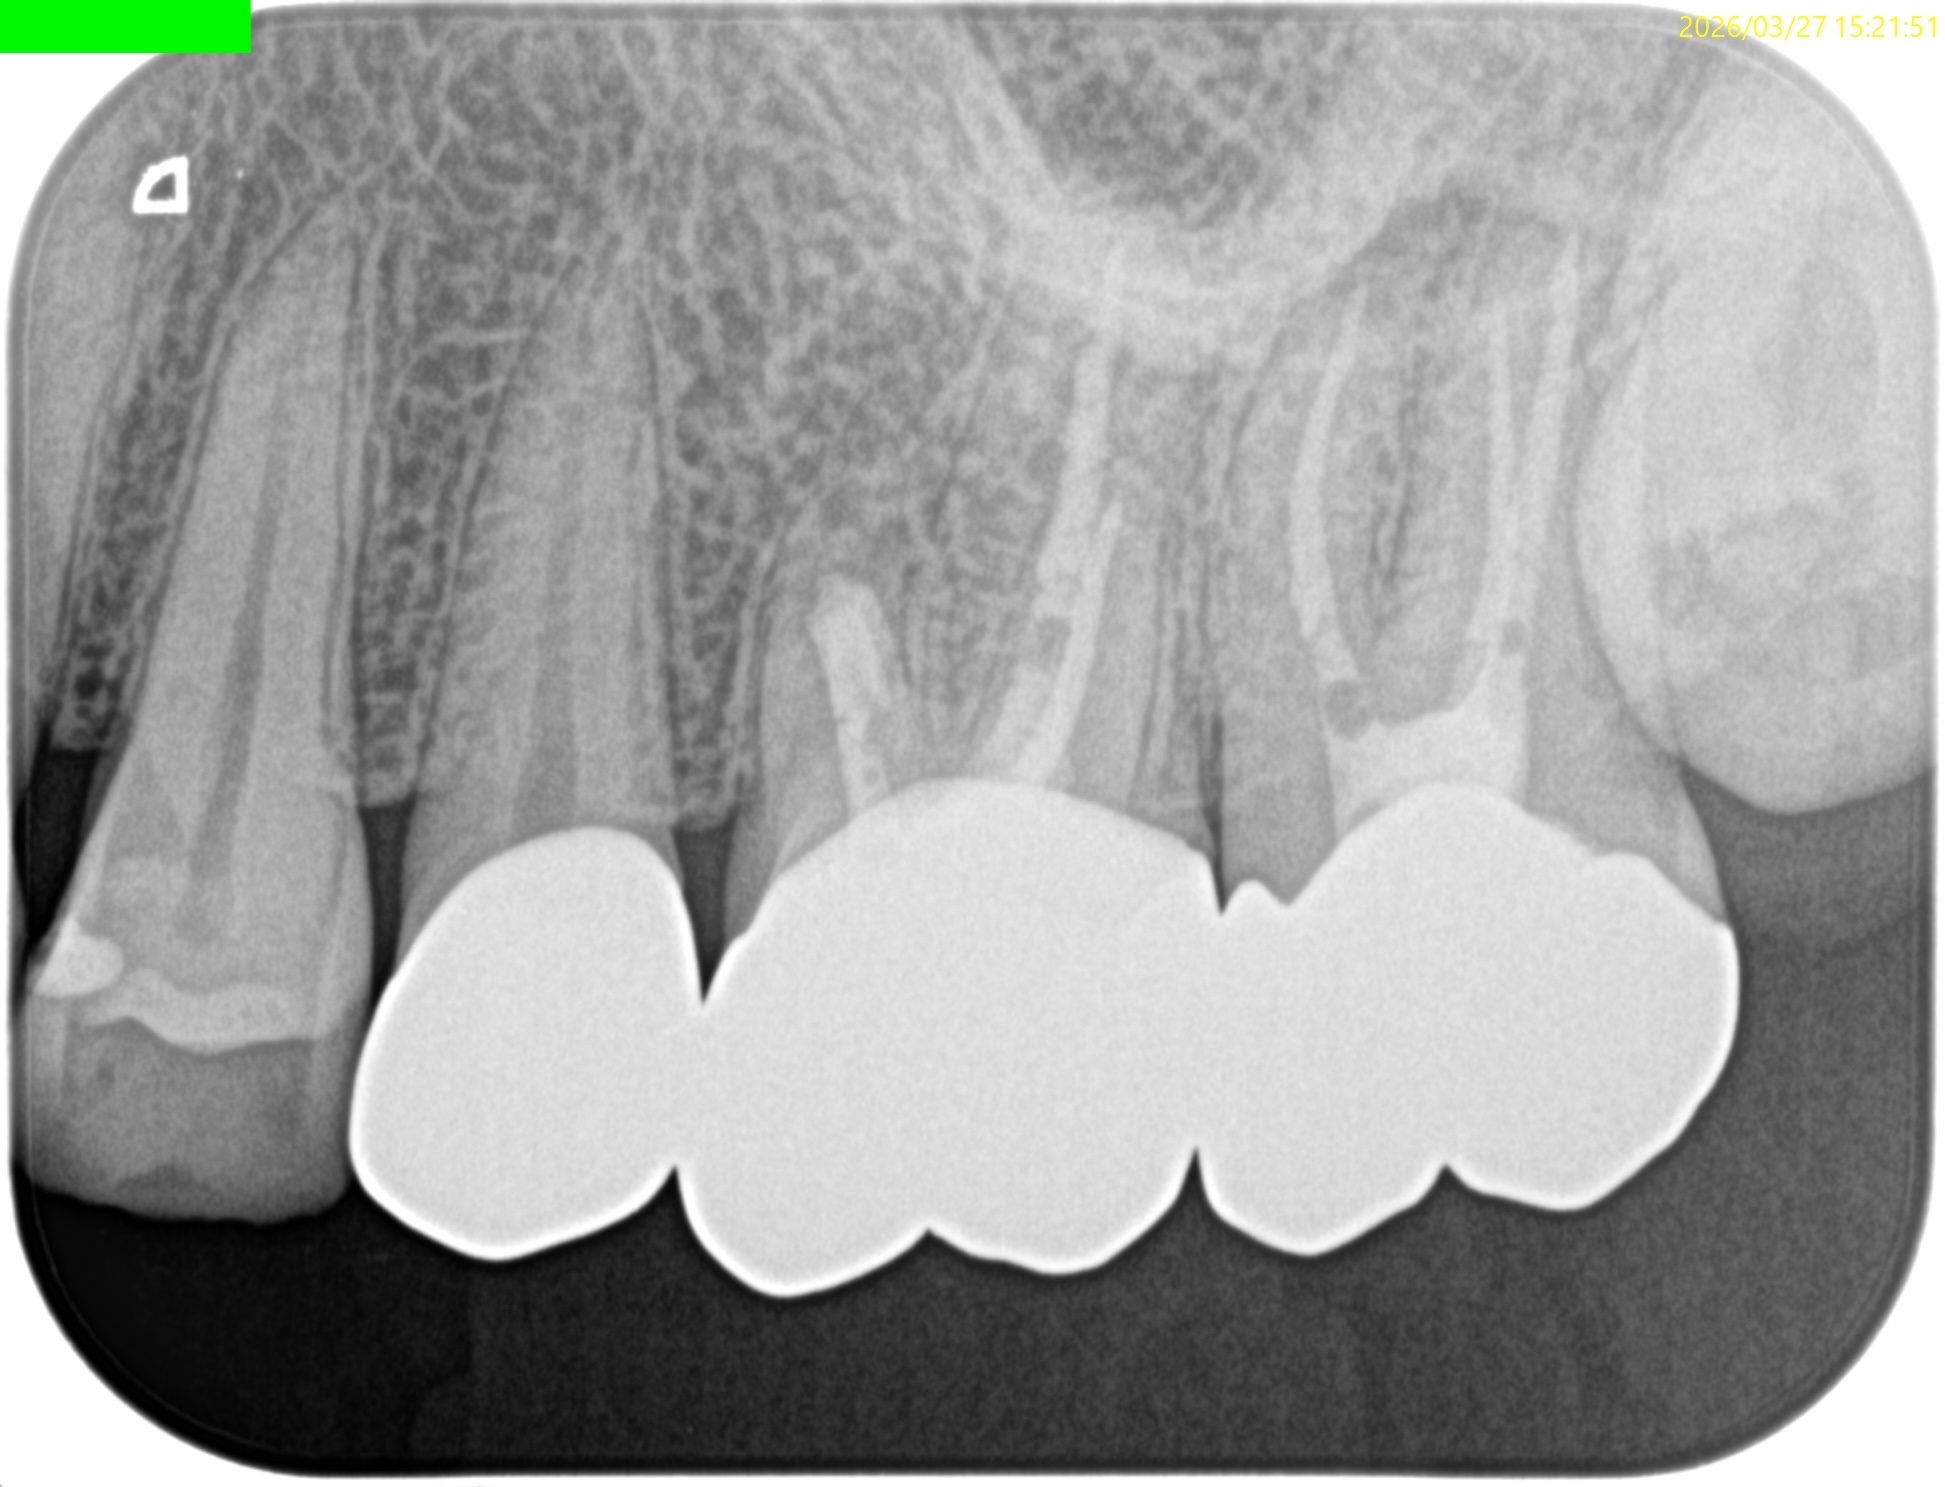

#14 Post-op 1yr recall(2026.3.27)

PA, CBCTを撮影した。

MB

DB

P

外科時と比較した。

問題は劇的に解消した。

ということでこの日で終診とさせていただいた。